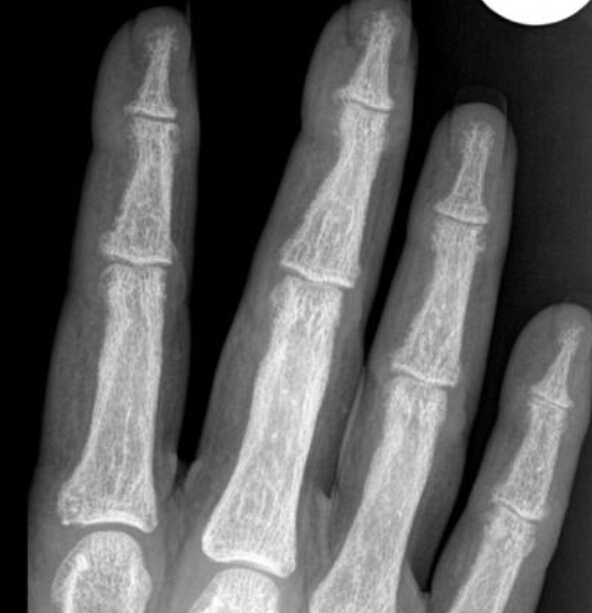

What is the diagnosis? What makes you think so?

Reflex sympathetic dystrophy

there is pretty severe demineralization and the joint spaces are good